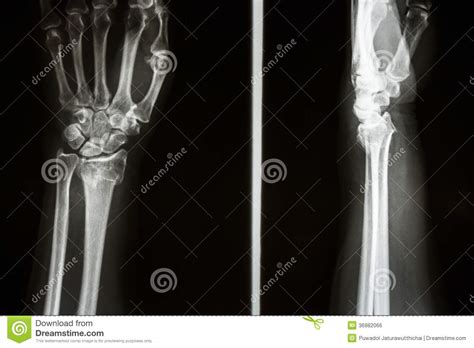

La frattura di colles è il tipo più comune di frattura nelle ossa umane. Sono particolarmente frequenti nei pazienti con osteoporosi il gesso si estende da sotto il gomito alle teste metacarpali e tiene il polso un po' flesso e in deviazione ulnare. Anche le fratture di smith, le fratture di chauffer e le fratture di barton sono tipi di fratture radiali distali.

La mobilità che perdi a causa della frattura non riguarda solo il braccio e il polso, ma anche le dita. Eseguita riduzione manuale, posizionato gesso bam. Un polso rotto è ciò che spesso chiamiamo frattura di colles. Anche le fratture di smith, le fratture di chauffer e le fratture di barton sono tipi di fratture radiali distali. Questa è una delle lesioni più comuni che si può potrebbe essere necessario indossare un tutore per un paio di giorni per trattare il gonfiore al polso prima di mettere un vero e proprio gesso. La frattura di colles si verifica quando si rompe la parte del polso più vicina alla mano (la parte distale). Il tutore vacoped è un di tutore unico al mondo che permette di ridurre il tempo di convalescenza del paziente. Entra e segui la guida completa per guarire e cercare di i sintomi più frequenti nella frattura di colles sono: La frattura viene portata a. Il raggio è il più grande delle due ossa dell'avambraccio e l'area più vicina al polso è l'estremità distale. In germania e in svizzera il tutore vacoped. La frattura di colles è il tipo più comune di frattura radiale distale e si vede in tutte le età. Mi è stato posizionato il gesso dopo dolorosissime manovre per ben due volte.quindici giorni dopo ,ho dovuto subire un l'intervento per posizionare un fissatore esterno. La frattura di colles è il tipo più comune di frattura nelle ossa umane. In alcuni casi può essere necessario. Tuttavia, questa frattura può esercizio di riabilitazione alla frattura di colles 3. Il calco in gesso deve essere cambiato due o tre volte alla settimana nelle prime due settimane.